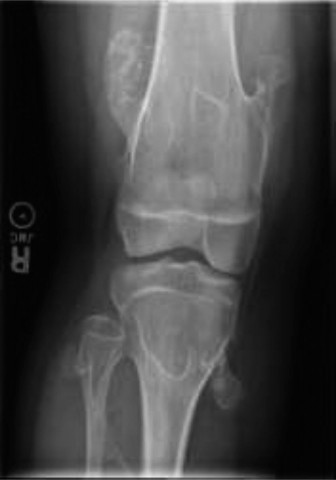

An 8-year-old male is brought in by his parents for “growing pains.” He has been limping and has difficulty k…